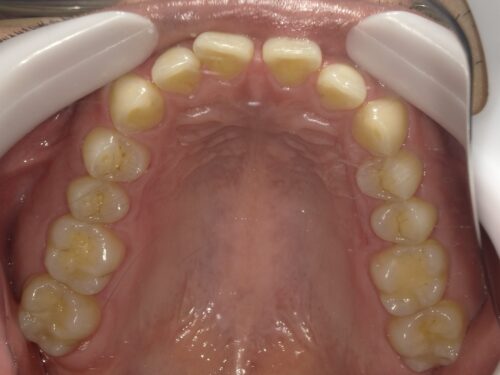

現在の状態です。

画像でどのくらいの隙間が空いているかの計測を行い、どのように歯を動かしていくかシミュレーションします。

患者さんにも見てもらい、修正点の確認をします。